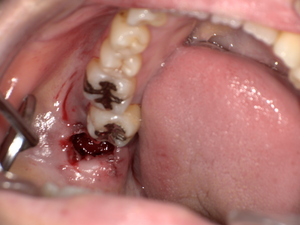

口腔扁平苔癬の主な症状|痛み・赤み・白斑などの見分け方

初期症状と進行症状の違い

初期:細かい白い網目状、軽度のかゆみや違和感

中期〜進行期:白板形成、赤み、潰瘍、強い痛み、出血などが出ることもあります。

組織検査(生検)が必要なケースとは?

白斑が厚く、患部が硬い、出血しやすい

痛みが強く、潰瘍がある

がん化のリスクを排除したい場合

このような場合には粘膜の一部を採取する生体検査(生検)が行われます。

【がん化の危険性】口腔扁平苔癬は口腔がんになる可能性がある?

口腔扁平苔癬のがん化率は文献によって異なりますが、0.5~2%程度と報告されています。長期・重症病変や潰瘍形成のある例では注意が必要です。

観察・経過観察が必要な理由